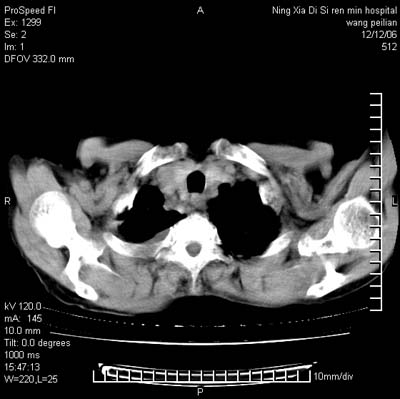

标题: CT5609:胸部:女77 病史不详 [打印本页]

标题: CT5609:胸部:女77 病史不详

两肺可见多个大小不等的结节,左侧有胸水,纵隔淋巴结增大,考虑是细支气管肺泡癌

两肺尖纤维索状影,两下肺结节块状影,且有钙化灶,右胸腔积液。考虑肺结核并胸膜炎。

两肺尖纤维索状影,两下肺结节块状影,且有钙化灶,右胸腔积液。考虑肺结核并胸膜炎肺间质纤维化

考虑:1、慢性支气管炎合并全小叶型肺气肿、间质纤维化;

2、双肺结核;

3、右侧胸膜炎(积液)。

1、双肺继发型肺结核(以纤维、增殖灶为主);

2、右侧胸腔积液;

3、其余符合老年肺改变。